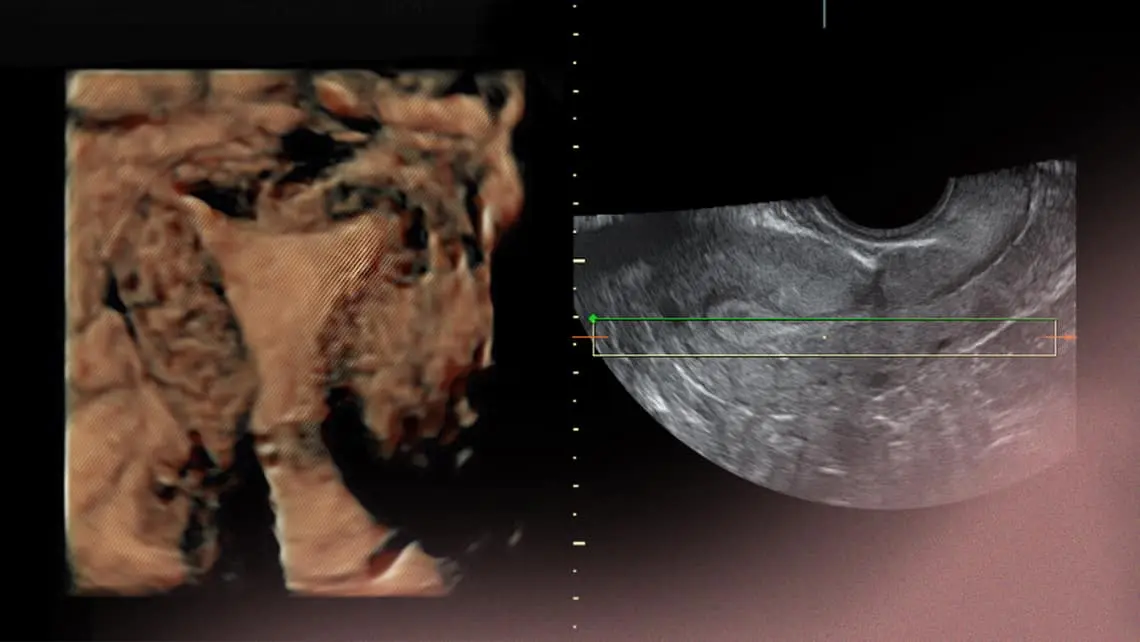

Wie wird die Dicke der Gebärmutterschleimhaut gemessen?

Die Dicke der Gebärmutterschleimhaut kann mit verschiedenen Verfahren gemessen werden, darunter:

- Ultraschall: Ein Ultraschalluntersuchung ist die häufigste Methode zur Messung der Gebärmutterschleimhaut.